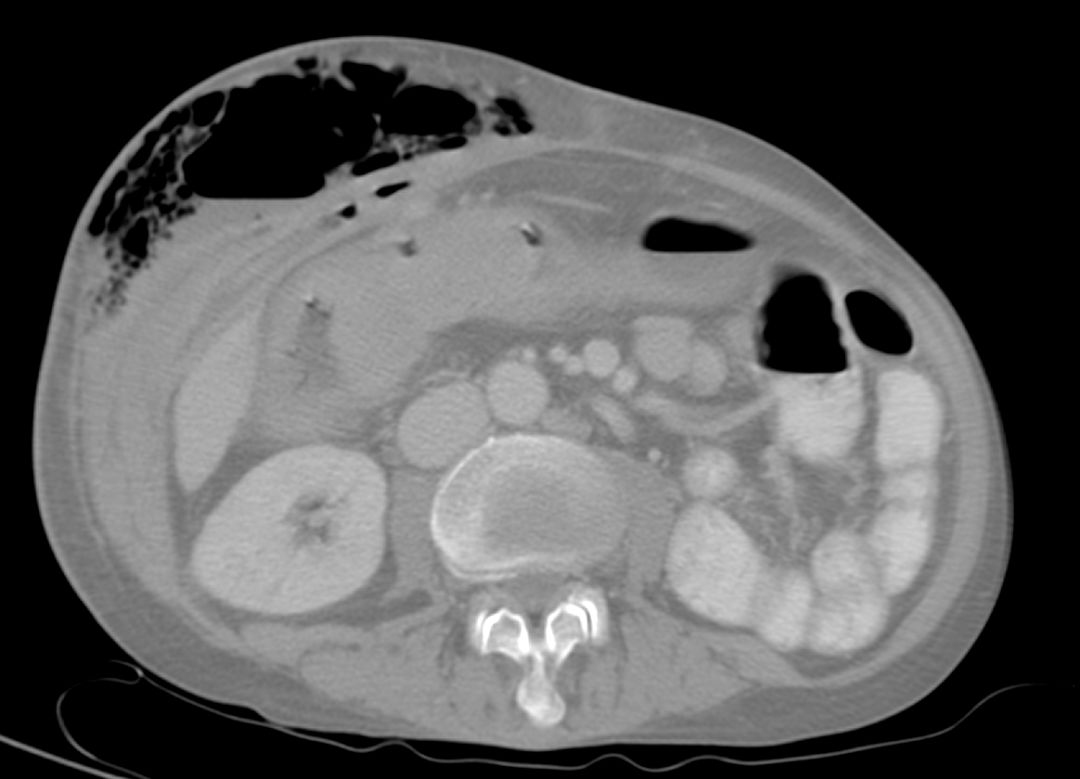

腹部CT伴右结肠皮肤瘘和相关的皮下气肿